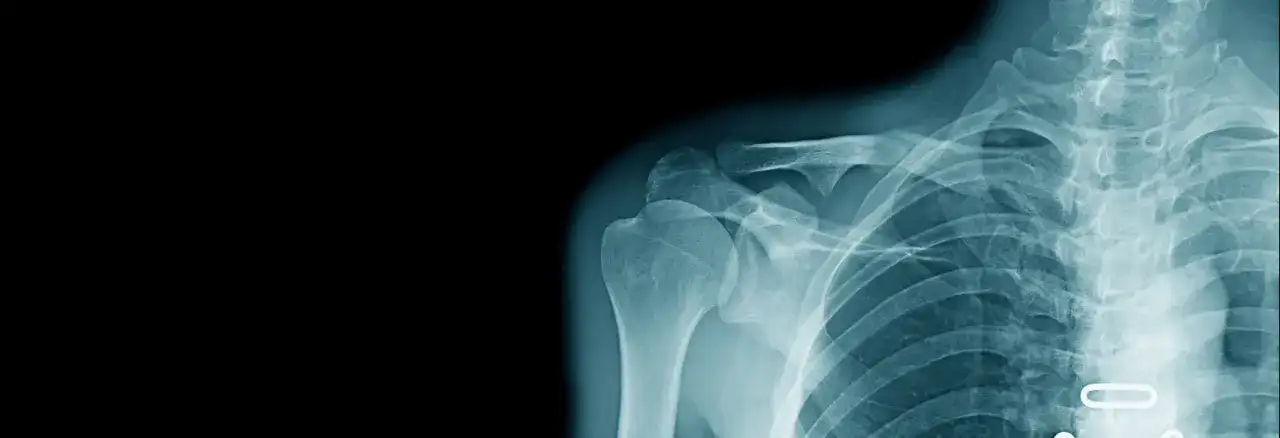

Złamanie nasady bliższej kości ramiennej - dowiedz się, czym jest uraz, objawy, diagnostyka i leczenie, a także plan rehabilitacji i rokowania.